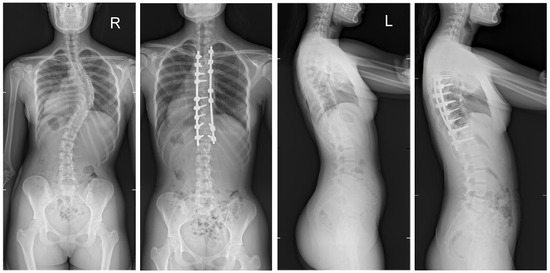

The mean (SD) operative times were recorded as 252 (62.4) minutes for the G1 patients and 344 (82.8) min for the patients in G2. The mean (SD) estimated blood loss levels were noted as 480 (288) mL for the patients in G1 and 632 (278) mL for G2. During statistical analysis, we found no statistically significant differences in either operative time or estimated blood loss between the study groups. The mean (SD) fusion levels were 10.2 (2.8) for G1, and 9.8 (3.2) for G2 (N.S.). The mean (SD) screw densities were noted as 75% (12) for the G1 group, and 75 (10) for the G2 group (N.S.). All analyzed data are presented in Table 1. Figure 1, Figure 2, Figure 3 and Figure 4 show X-rays of exemplary patients with idiopathic scoliosis after surgical treatment from G1 and G2.

Figure 4.

X-rays of a 15-year-old girl with AIS, treated with smaller (standard) screw size of 5.5 and 2 titanium rods of 5.5 mm (G1). X-rays show curve before surgery and correction after surgical treatment.

The correction of spinal deformities using modern systems based on the CD technique enriched with osteotomy techniques of the posterior column of the spine provides powerful opportunities for the correction and stabilization of curvatures [4,8,10,11,12,13]. Many details of implants have evolved and been improved, such as the implant profile, screw head stiffness, mobility in the sagittal axis, and its multi-axial nature, to obtain the best possible correction results [20,21,37,38]. The quality of the rod used is important in three-plane correction, i.e., the metal alloy (titanium, cobalt–chrome) and its diameter, which affects its ability to reproduce the sagittal and frontal balance of the spine [17,18,19,20,21]. It is known from other biomechanical studies that the larger the screw diameter, the better the stabilization and the lower the risk of screw removal and implant loosening [20,23,39,40,41]. For the surgical treatment of AIS, we received excellent outcomes using a system based on CD instrumentation in terms of three-dimensional correction of the spine (Figure 1, Figure 2, Figure 3 and Figure 4 show X-rays of exemplary patients with idiopathic scoliosis after surgical treatment from G1 and G2), the coronal and sagittal planes, derotation, and the clinical outcomes [11,12,13]. It should be emphasized that the correction possibilities of spinal deformation are influenced by other factors that we did not analyze, such as bone quality, so we focused on assessing the results of surgical treatment based on the sizes of the screws and rods used [39,40,41]. Also, the flexibility of the spine assessed on bending films is the main factor influencing the achievement of correction, as well as the loss of correction [42].